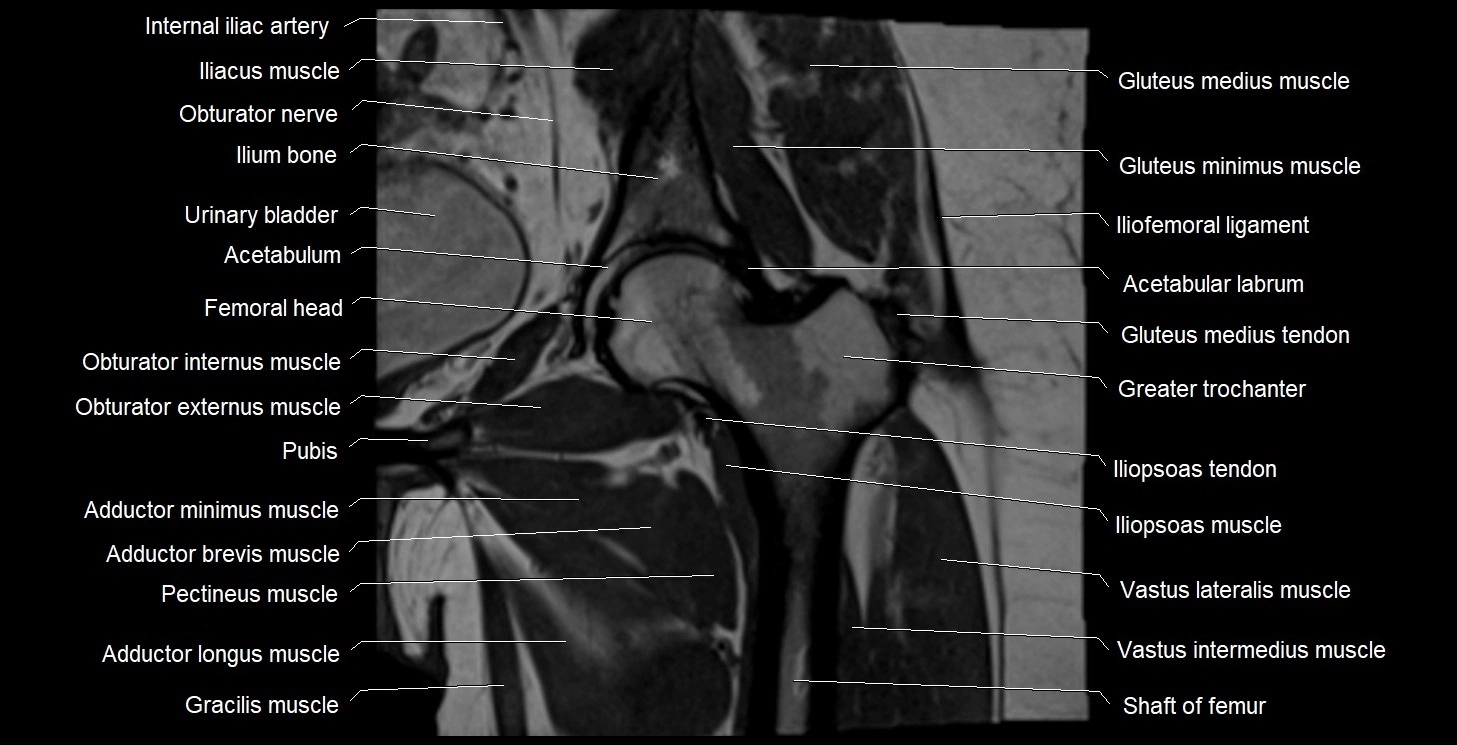

- Acetabulum

- External iliac artery

- External iliac vein

- Femoral nerve

- Genitofemoral nerve

- Gluteus medius muscle

- Gluteus minimus muscle

- Gracilis muscle

- Greater trochanter

- Head of femur

- Iliofemoral ligament

- Iliopsoas muscle

- Iliopsoas tendon

- Ilium bone

- Obturator externus muscle

- Obturator internus muscle

- Pectineus muscle

- Psoas major muscle

- Round ligament of uterus

- Sigmoid colon

- Urinary bladder

- Uterine artery

- Uterus

- Vastus intermedius muscle

- Vastus lateralis muscle